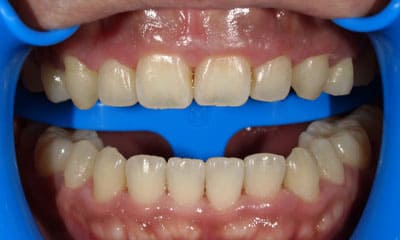

症例

+

藤沢デンタルオフィスのホワイトニング術前 藤沢デンタルオフィスのホワイトニング術後

術前

術後